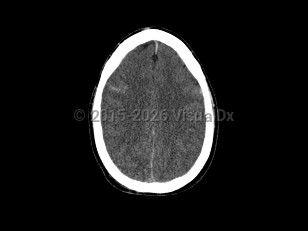

Cerebral edemaCerebral edema

Hydrocephalus

Idiopathic intracranial hypertensionIdiopathic intracranial hypertension

PapilledemaPapilledema